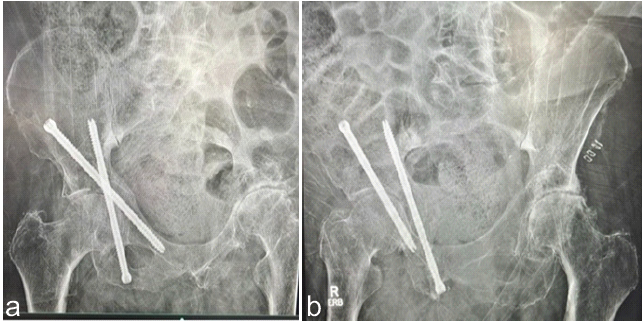

Intraoperatively, the bone was noted to be markedly osteopenic. All wires were removed, wounds were irrigated and closed in a layered fashion, and sterile dressings were applied. The patient was hemodynamically stable for the entire duration of the procedure and was transferred to the intensive care unit in stable condition post-operatively. Post-operatively, he received antibiotics according to our institutional protocol and deep vein thrombosis prophylaxis as directed by the primary medical team with Lovenox. He maintained touch down weight bearing (TDWB) as tolerated on the right lower extremity for 6 weeks, with immediate range-of-motion as tolerated (ROMAT) to minimize stiffness. At his first follow-up visit, 4-weeks post-operatively, Judet views of the pelvis demonstrated maintained alignment of the acetabulum with no evidence of hardware loosening or failure as seen in Fig. 3a and b. Incisions were fully healed and the plan was to continue TDWB with ROMAT and follow-up in 3 weeks for repeat imaging.

Figure 3: (a and b) 4-week postoperative Judet view radiographs.